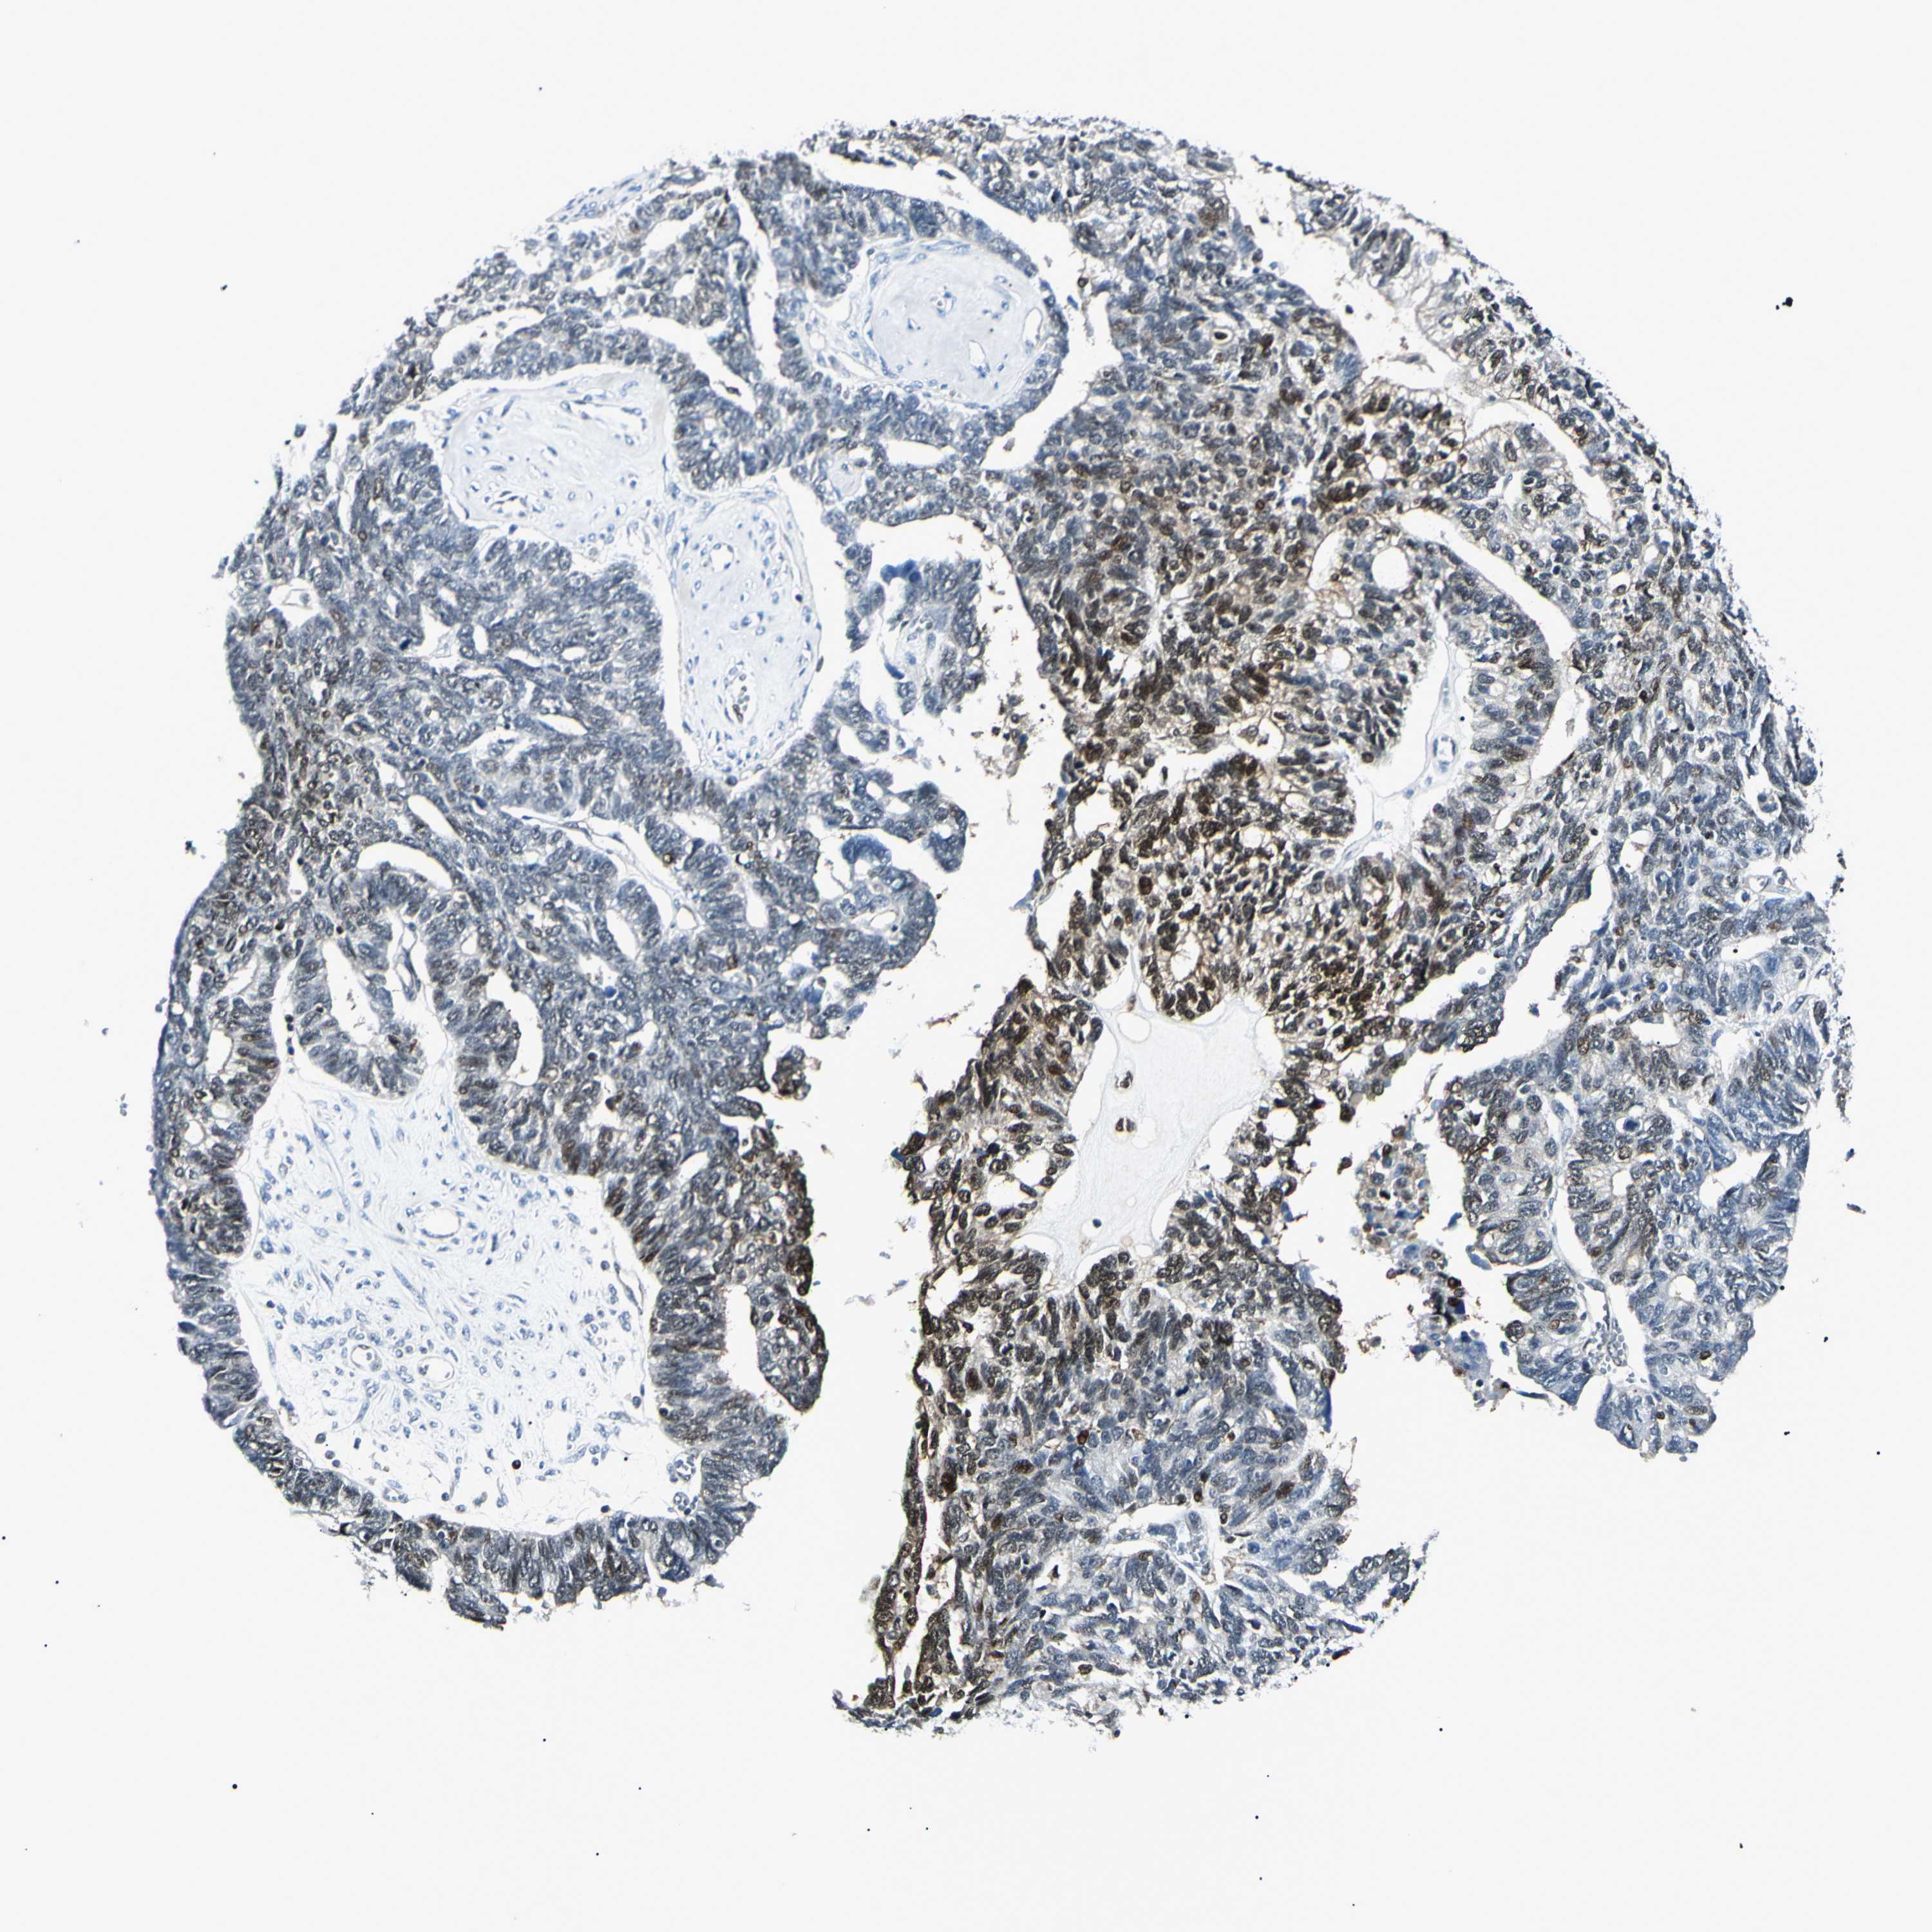

OVARIAN CANCER - Protein expressioni

A mouse-over function shows sample information and annotation data. Click on an image to view it in a full screen mode. Samples can be filtered based on level of antibody staining by selecting one or several of the following categories: high, medium, low and not detected. The assay and annotation is described here.

Note that samples used for immunohistochemistry by the Human Protein Atlas do not correspond to samples in the TCGA dataset.

Antibody stainingi

Antibody staining in the annotated cell types in the current human tissue is reported as not detected, low, medium, or high, based on conventional immunohistochemistry profiling in selected tissues. This score is based on the combination of the staining intensity and fraction of stained cells.

Each image is clickable and will lead to virtual microscopy that enables deeper exploration of all samples and also displays staining intensity scores, fraction scores and subcellular localization as well as patient and tissue information for each sample.

Antibody HPA045385

Antibody HPA073644

Antibody HPA073656

Antibody CAB010065

Staining

High

Medium

Low

Not detected

Intensity

Strong

Moderate

Weak

Negative

Quantity

>75%

75%-25%

<25%

None

Location

Nuclear

Cytoplasmic/membranous

Cytoplasmic/membranous,nuclear

Cystadenocarcinoma, serous, NOS

Carcinoma, NOS

Cystadenocarcinoma, mucinous, NOS

Carcinoma, endometroid